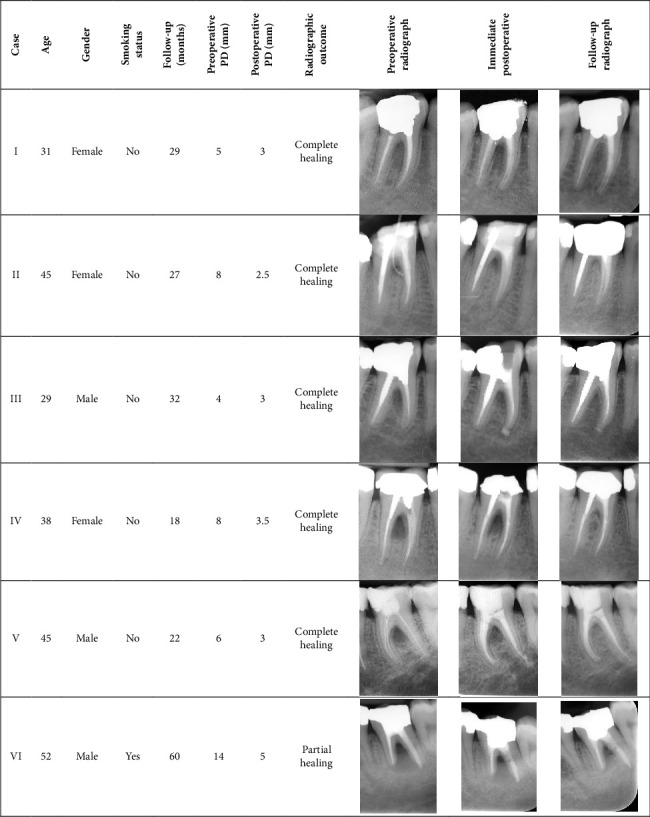

Furcation defects pose significant challenges in endodontic and periodontal therapy due to their complex anatomy and limited accessibility. Achieving a reliable seal at the apical/cervical/coronal levels is critical for long-term treatment success. This case series investigates the use of calcium-silicate biomaterials, specifically calcium-enriched mixture (CEM) cement, as cervical sealants in the nonsurgical management of furcation defects with endodontic origin, evaluating their regenerative potential and clinical applicability. Six endodontically treated teeth with furcation defects were included. All cases had undergone orthograde root canal therapy in the past and then were nonsurgically retreated with CEM cement placed as a cervical seal for this report. Baseline and follow-up evaluations, conducted over an average period of 31 months, assessed the clinical parameters of probing depths, furcation involvement, and radiographic evidence of healing. Radiographically, five cases demonstrated complete healing/regeneration, and one case showed partial resolution of the furcal lesion. Improvements in periodontal parameters, including lesser probing depths and elimination of bleeding and discharge, were observed across all cases, resulting in restored functionality of the affected teeth. The results suggest that CEM cement was an effective cervical sealing biomaterial for the nonsurgical management of furcation defects with endodontic origin. These findings highlight the potential of bioactive endodontic materials in minimally invasive dental therapies. Further studies with larger sample sizes and long-term follow-ups are needed to validate these findings.